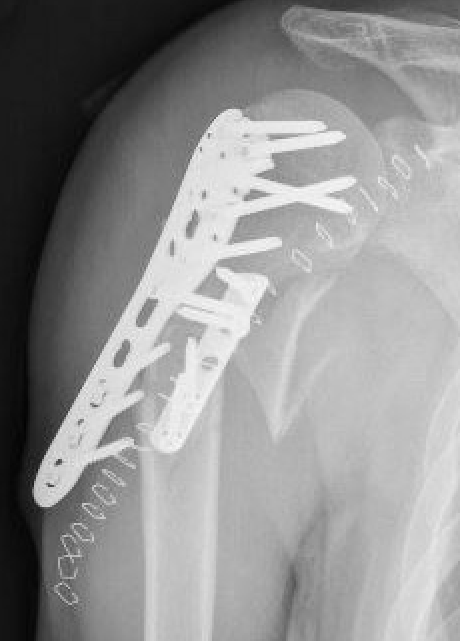

Plate

- narrow large fragment 4.5 mm DCP / long Philos proximal humeral plate

- minimum 6 cortices above and below

- can consider dual plate

- 4.5 mm plate with 6 cortices above and below

- if use 3.5 mm long proximal humeral plate, suggest 8 cortices below

- consider dual plating in proximal fractures with insufficient fixation, or in poor bone quality